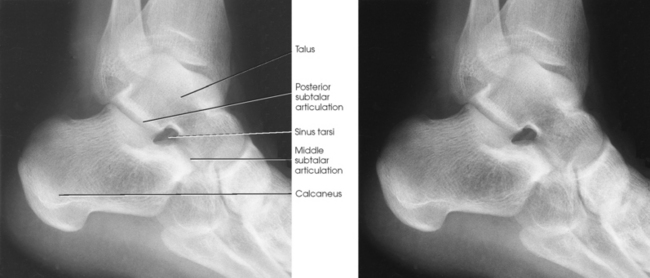

The calcaneus is the largest and strongest tarsal bone (Fig. 6-3). Some texts refer to it as the os calcis. It projects posteriorly and medially at the distal part of the foot. The long axis of the calcaneus is directed inferiorly and forms an angle of approximately 30 degrees. The posterior and inferior portions of the calcaneus contain the posterior tuberosity for attachment of the Achilles tendon. Superiorly, three articular facets join with the talus. They are called the anterior, middle, and posterior facets. Between the middle and posterior talar articular facets is a groove, the calcaneal sulcus, which corresponds to a similar groove on the inferior surface of the talus. Collectively, these sulci constitute the sinus tarsi. The interosseous ligament passes through this sulcus. The medial aspect of the calcaneus extends outward as a shelflike overhang and is termed the sustentaculum tali. The lateral surface of the calcaneus contains the trochlea.

The calcaneus supports the talus and articulates with it by an irregularly shaped, three-faceted joint surface, forming the subtalar joint. This joint is classified as a synovial gliding joint. Anteriorly, the calcaneus articulates with the cuboid at the calcaneocuboid joint. This joint is a synovial gliding joint. The talus rests on top of the calcaneus (see Fig. 6-12). It articulates with the navicular bone anteriorly, supports the tibia above, and articulates with the malleoli of the tibia and fibula at its sides.

Each of the three parts of the subtalar joint is formed by reciprocally shaped facets on the inferior surface of the talus and the superior surface of the calcaneus. Study of the superior and medial aspects of the calcaneus (see Fig. 6-3) helps the radiographer to understand better the problems involved in radiography of this joint.

The intertarsal articulations are as follows:

Isherwood1 devised a method for each of the three separate articulations of the subtalar joint: (1) a medial rotation foot position to show the anterior talar articulation, (2) a medial rotation ankle position to show the middle talar articulation, and (3) a lateral rotation ankle position to show the posterior talar articulation. Feist and Mankin2 later described a similar position.

Structures shown: The resulting image shows the anterior subtalar articulation and an oblique projection of the tarsals (Fig. 6-86). The Feist-Mankin method produces a similar image representation.

Structures shown: The resulting image shows the middle articulation of the subtalar joint and an “end-on” projection of the sinus tarsi (Fig. 6-88).

Structures shown: The resulting image shows the posterior articulation of the subtalar joint in profile (Fig. 6-90).